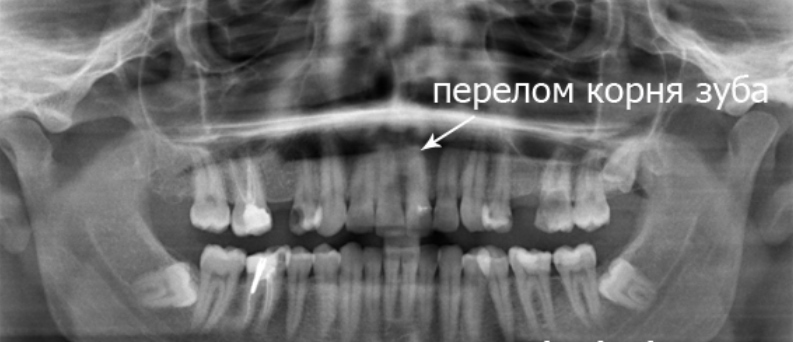

Наиболее информативным методом диагностики является рентгенологическое исследование.

- перелом корня зуба.

При переломе коронки зуба в большинстве случаев заметен ее дефект. При переломе корнязуба часто имеет место патологическая подвижность. Зондирование и перкуссия обычно усиливают болевые ощущения. В результате кровоизлияния коронка может приобрести розоватый оттенок, обусловленный нарушением целостности сосудов пульпы и проникновения эритроцитов в дентинные канальцы.

Перелом корня зуба в ряде случаев связан с установкой ортопедических конструкций – металлического штифта или вкладки. В подобных случаях корень раскалывается вдоль. Травма происходит либо непосредственно во время врачебных манипуляций, либо после чрезмерной механической нагрузки на зуб (в частности – при завышении прикуса).